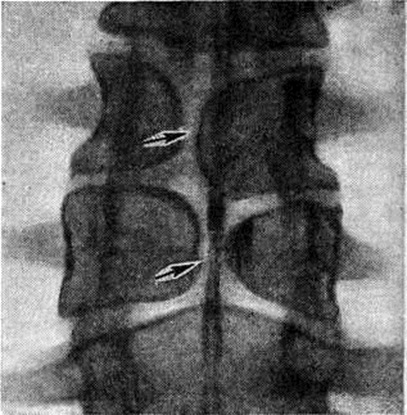

Рентген шейных позвонков при спина бифида

Раздел: Фотозарисовки